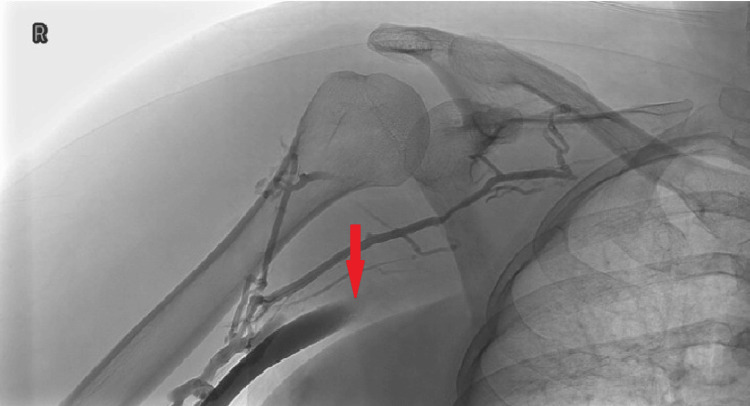

We discuss the case of a 36-year-old woman who presented with persistent right upper limb swelling and pain. A previous negative D-dimer (434 µg/L (normal range <500 µg/L)) resulted in an inappropriate discharge, despite a significant past medical history. The patient was sent for a right upper limb ultrasound Doppler scan due to persistent pain, and a clot in the right supraclavicular subclavian vein was observed, confirming the diagnosis of Paget-Schroetter syndrome (PSS). The clot was successfully removed under the vascular team in Cardiff without any post-op complications. The literature review demonstrates that PSS should be suspected mostly on a clinical basis; the literature does not support the use of a D-dimer to support a suspected upper limb deep vein thrombosis (DVT), as this could delay vital treatment for the patient, as demonstrated in this case.